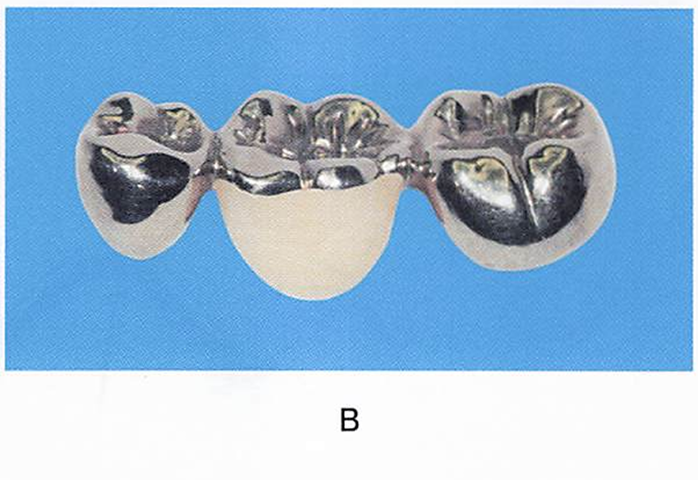

1歯欠損に応用される2種類の補綴装置の写真を別に示す。Aと比較したBの特徴はどれか。2つ選べ。

a.違和感が少ない。

b.侵襲性が小さい。

c.咀嚼能率が高い。

d.取り外しが容易である。

解答を見る

a.c